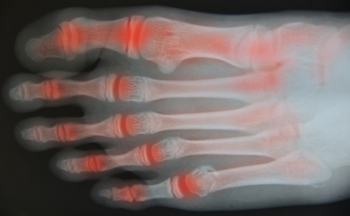

Arthritis is a condition that causes inflammation and stiffness in the joints, often leading to pain and reduced mobility. Common types include osteoarthritis, which results from wear and tear, and rheumatoid arthritis, an autoimmune disorder. Risk factors include aging, genetics, obesity […]